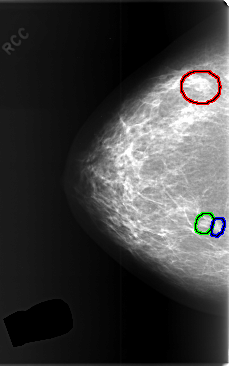

C_0374_1.RIGHT_CC

RIGHT_CC LINES 5848 PIXELS_PER_LINE 3656 BITS_PER_PIXEL 12 RESOLUTION 50 OVERLAY

FILE: C_0374_1.RIGHT_CC.OVERLAY

TOTAL_ABNORMALITIES 3

ABNORMALITY 1

LESION_TYPE MASS SHAPE LOBULATED MARGINS CIRCUMSCRIBED

ASSESSMENT 3

SUBTLETY 5

PATHOLOGY BENIGN

ABNORMALITY 2

LESION_TYPE MASS SHAPE OVAL MARGINS CIRCUMSCRIBED

ABNORMALITY 3

LESION_TYPE MASS SHAPE ROUND MARGINS CIRCUMSCRIBED